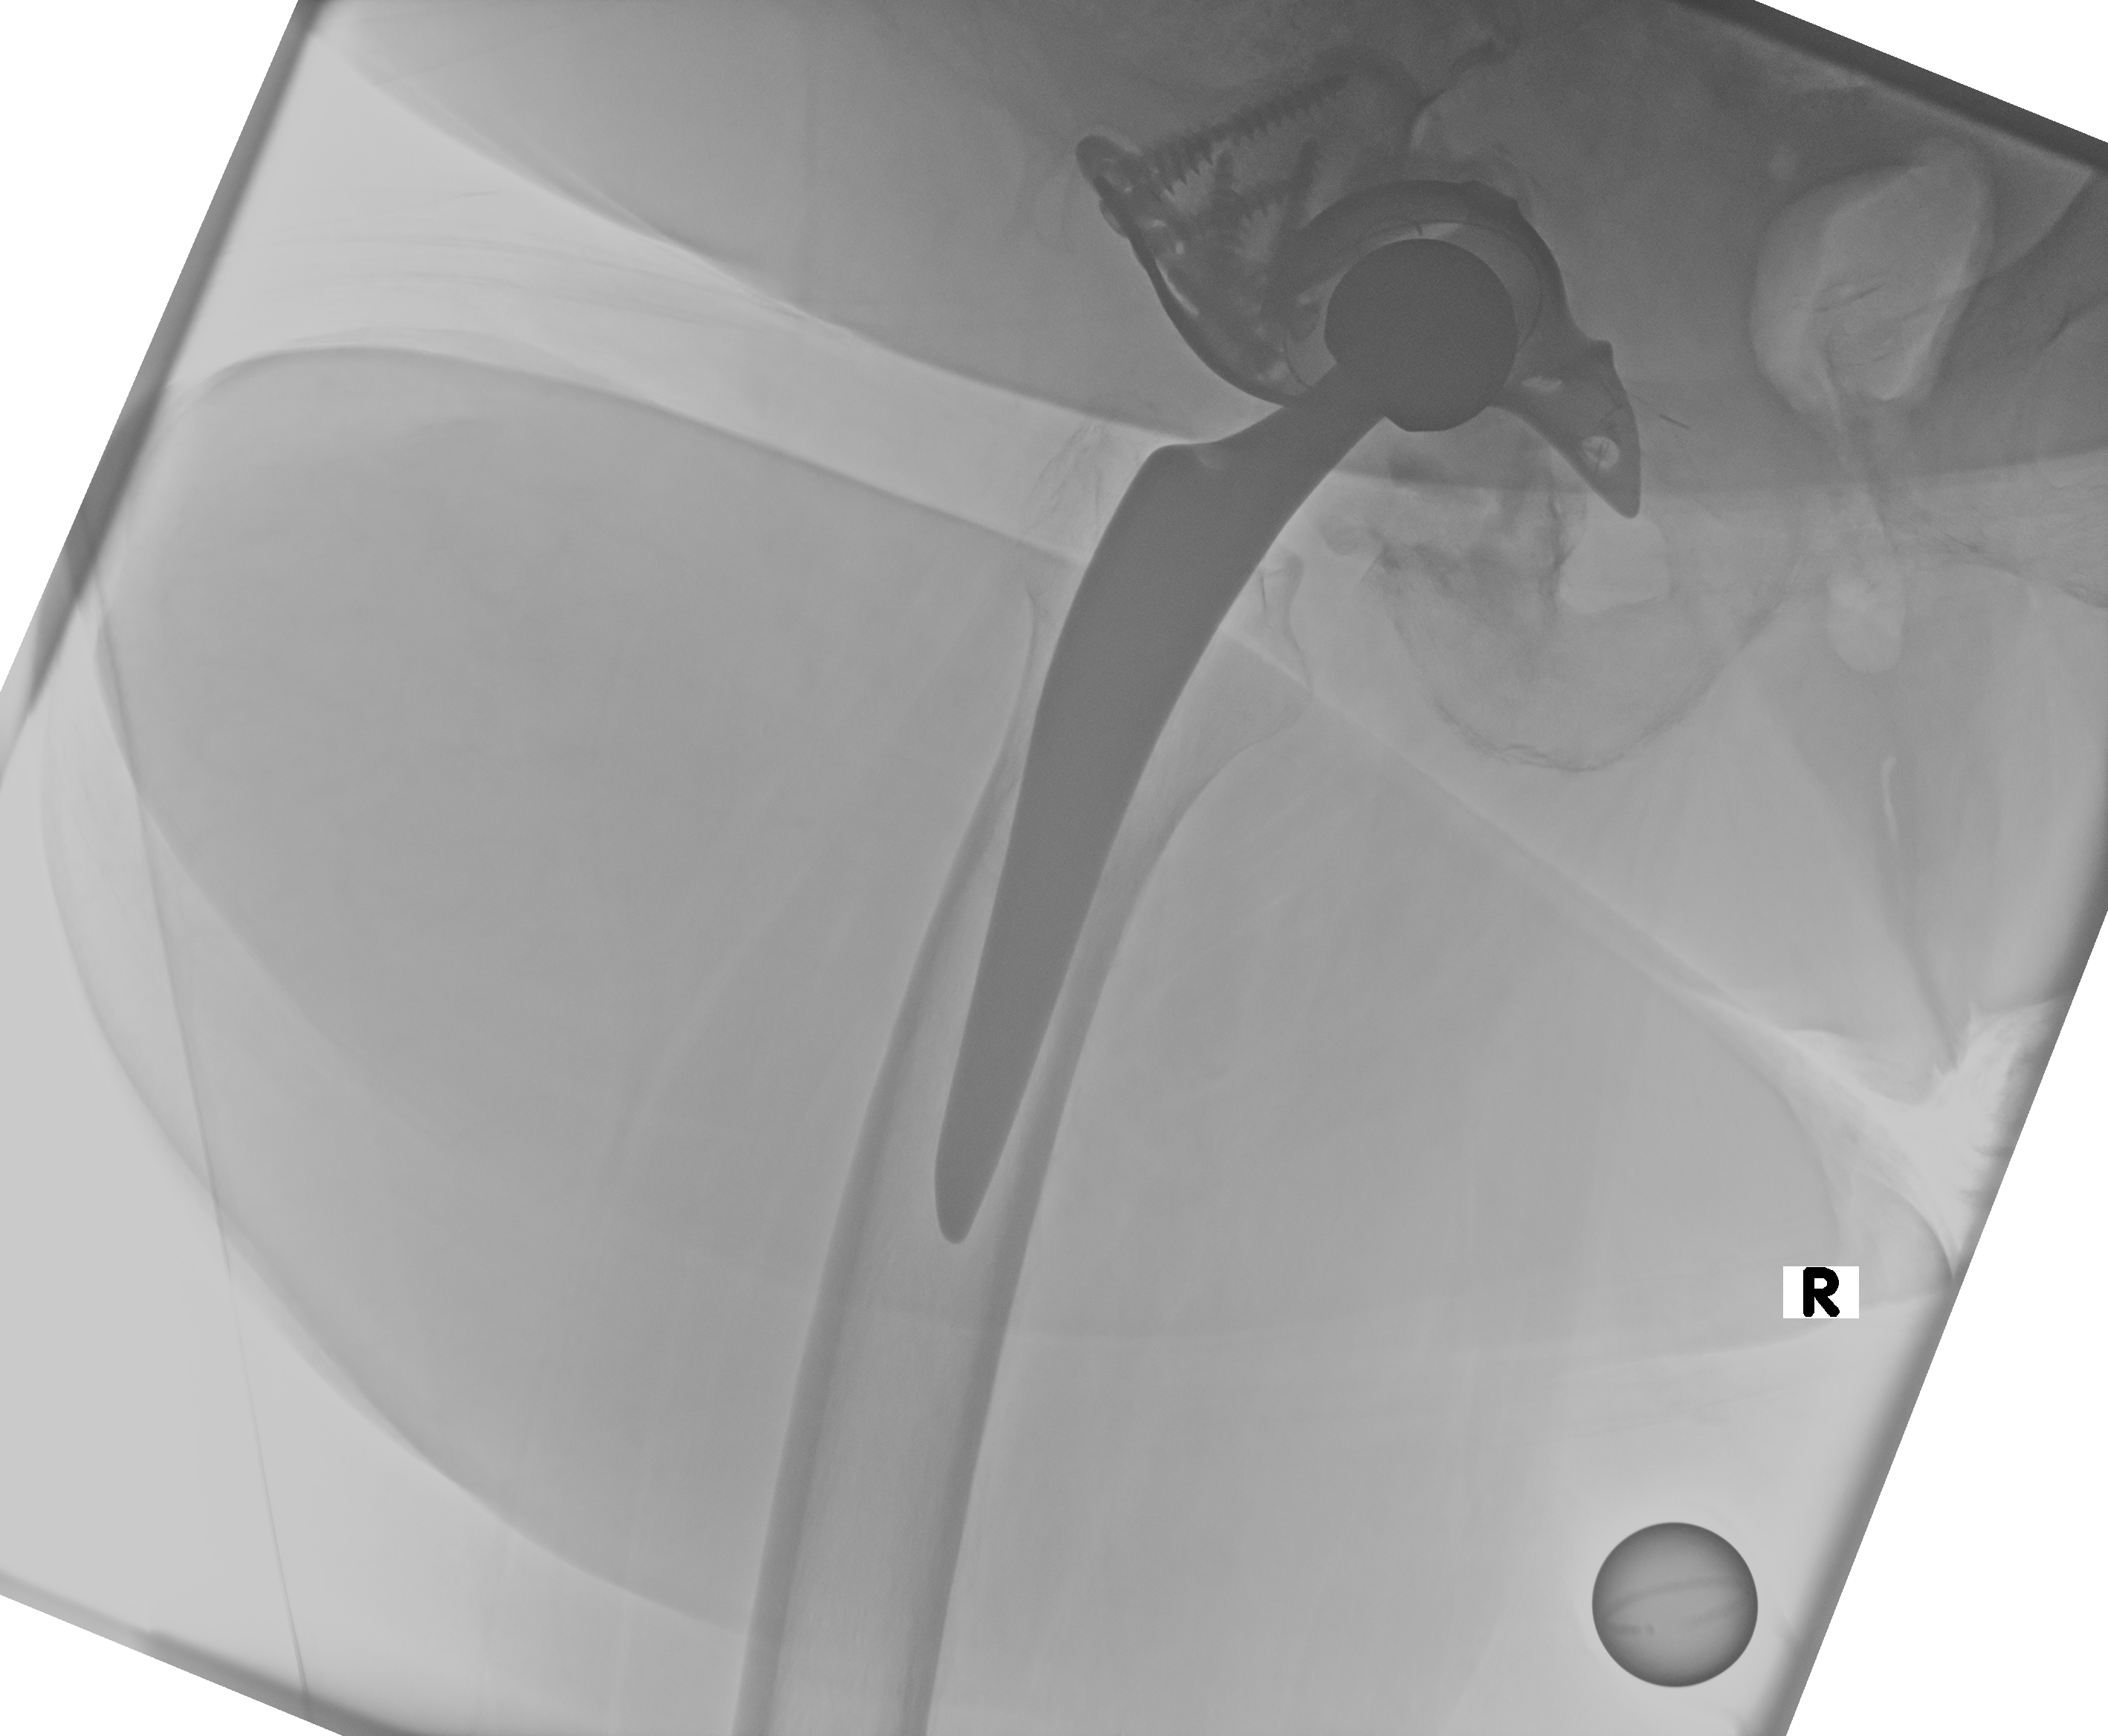

24.02.2026 - Neue TEP

Röntgen Februar 2026

Neue Hüft-TEP rechts nach Wiedereinbau

24.02.2026 - Neue TEP!

Becken 2026

Verlauf: Die Luxation/Pfannendislokation führte zur stationären Aufnahme im Universitätsklinikum Heidelberg (28.12.2025). Am 30.12.2025 wurde die TEP entfernt und ein Spacer implantiert. Infektnachweis: Enterococcus faecalis. Am 19.02.2026 wurde die neue Prothese erfolgreich eingebaut (stationär bis 05.03.2026). Komplikationsloser Verlauf, regelrechte Implantatlage im Röntgen. Entlassung mit 20kg Teillast, Amoxicillin für 6 Wochen. Wiedervorstellung am 09.04.2026.

24.02.2026 - Postoperativ

Röntgen Becken + Hüfte rechts (Kontrolle nach Wiedereinbau)

3 Aufnahmen | Becken tief + 2x Hüfte Lauenstein | 5 Tage nach OP

24. Februar 2026

Postoperative Röntgenkontrolle

Röntgen Becken tief + 2x Hüfte Lauenstein R – Kontrolle 5 Tage nach Wiedereinbau.

24.02.2026 - POSTOP

Röntgen Becken tief (nach Wiedereinbau)

DICOM

Kontrolle Becken 5 Tage nach Wiedereinbau TEP

Röntgen Hüfte Lauenstein R (1)

Kontrolle Hüfte 5 Tage nach Wiedereinbau TEP

Röntgen Hüfte Lauenstein R (2)